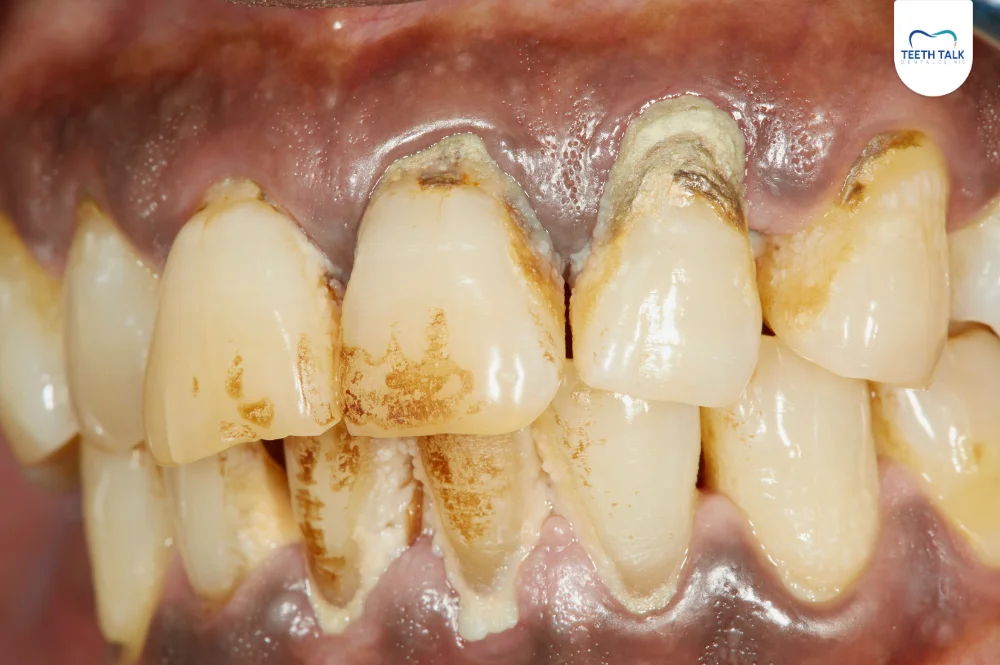

หินปูน (Dental Tartar) คือคราบแข็งสีเหลืองน้ำตาลไปจนถึงสีดำ ที่เกาะแน่นอยู่บนผิวฟันและบริเวณขอบเหงือก มันเกิดจากการที่แร่ธาตุในน้ำลายเข้าไปตกตะกอนทับถมบนคราบจุลินทรีย์ (คราบพลัค) ที่ไม่ถูกกำจัดออกไป เมื่อคราบนี้แข็งตัวแล้ว จะไม่สามารถแปรงฟันหรือขัดออกได้เอง จำเป็นต้องให้ทันตแพทย์กำจัดออกด้วยเครื่องมือเฉพาะทางเท่านั้น

- คราบสีเหลืองหรือน้ำตาล : สังเกตเห็นคราบสีเหลืองเข้มไปจนถึงสีน้ำตาล เกาะบริเวณคอฟัน โดยเฉพาะฟันหน้าล่างด้านใน

- ผิวฟันสาก : ใช้ลิ้นดุนจะรู้สึกว่าผิวฟันไม่เรียบ แต่มีความสาก หรือมีคราบแข็งเกาะอยู่